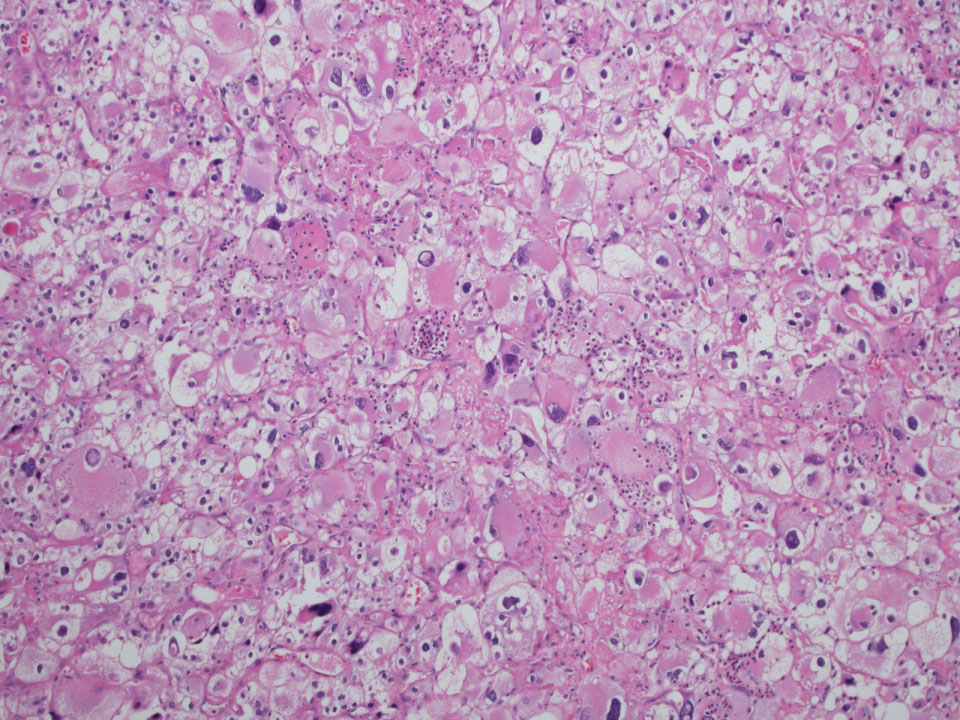

Consensus grade: WHO/ISUP grade 4

Rhabdoid area in a clear cell RCC |

Rhabdoid cells |